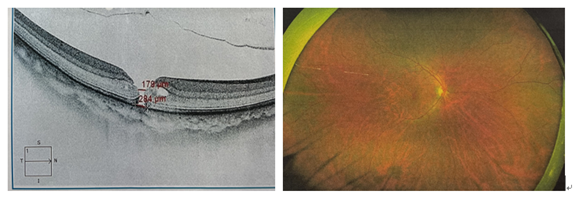

△术前黄斑OCT,黄斑裂孔明显,284μm

△手术成功,黄斑裂孔愈合